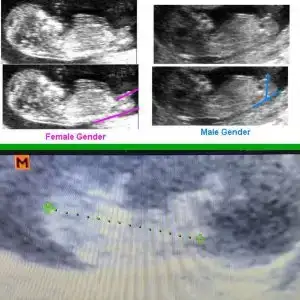

dr soylemeden siz gorun genital nub teorisi ( bebegin cinsiyeti)

Bence erkek :))Merhabalar arkadaşımın bebeği 11+3 te tahmin eder misiniz çok merak ediyoruzIkra meyra

Net değil emin olamadım hiç 12 13 haftalar olursa paylaşınBanada tahmin yaparmisiniz

Nubu tam görünmüyor başka varsa USG paylaşın boyutsuz olursa daha iyi olur

Erkek gibi ama siz yine USG olursa paylasinMerhabalar arkadaşımın bebeği 11+3 te tahmin eder misiniz çok merak ediyoruzIkra meyra

Net değil nubu olursa 11 12 13 haftalarda USG paylaşın